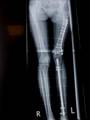

Pre Op

X-ray (Left femur)

osteolytic lesion

(?) osteosarcoma